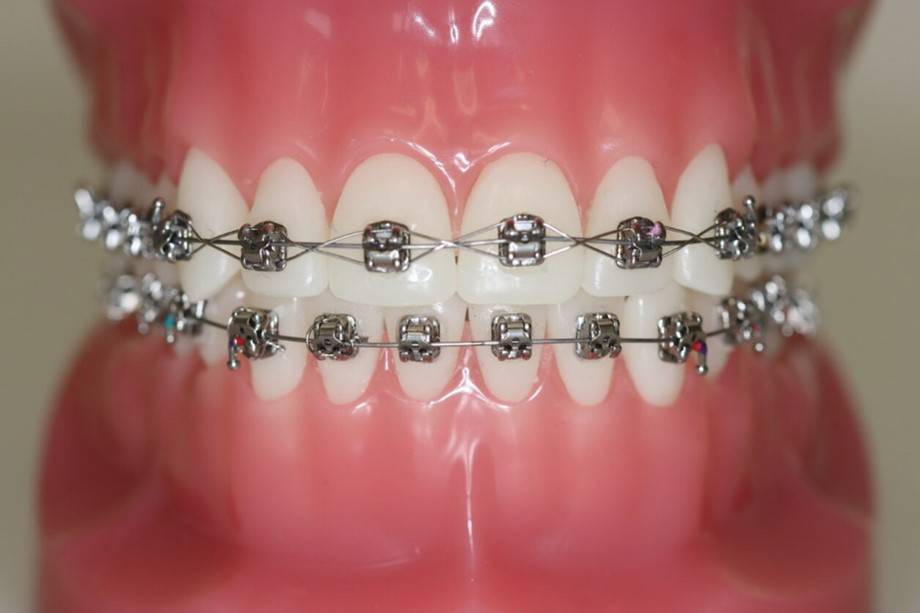

Brackets eller ”togskinner” bliver limet fast på tænderne. Oftest er det nødvendigt med fastsiddende bøjler i både overkæben og underkæben.